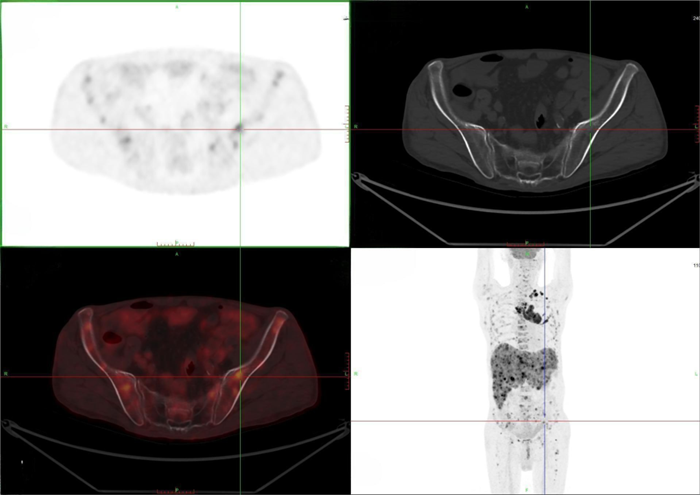

骨盆多發(fā)轉(zhuǎn)移

之后,徐伯伯來到我院進行PET/CT檢查,發(fā)現(xiàn)左肺上葉惡性結(jié)節(jié),為原發(fā)灶,并引起縱隔多發(fā)淋巴結(jié)轉(zhuǎn)移。同時,肝臟、全身多處骨骼、頸部、腹部、腹股溝等多處的淋巴結(jié)出現(xiàn)了遠處轉(zhuǎn)移。